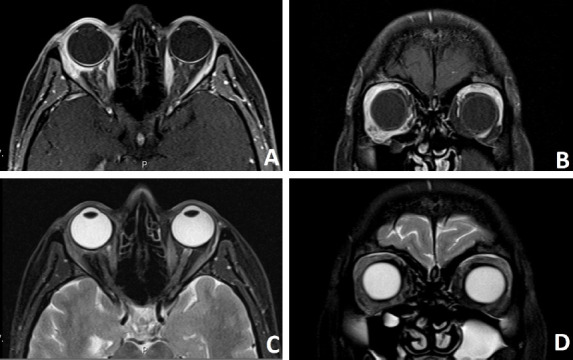

转移性疾病是眼眶肿瘤的一个相对罕见的病因。虽然有许多不同类型的原发性恶性肿瘤被记录在案,但其中以肺癌和乳腺癌最为常见。本文报告了三例乳腺癌眼眶转移病例。第一例患者无原发性恶性肿瘤病史,最初表现为晚期乳腺癌眼眶转移。第二例患者曾接受新辅助化疗、乳房切除术和辅助放疗。经诊断,该病的复发是通过有症状的眼眶转移累及外侧直肌。第三例患者曾接受乳房切除术、辅助放疗和激素治疗。考虑到即使没有诊断出原发性恶性肿瘤的患者也可能出现眼眶转移,眼科医生对此问题的认识至关重要。

Metastatic disease is a relatively rare cause of orbital tumors. While many different types of primary malignancies have been documented, lung and breast cancers are the most prevalent ones among them. Herein, three cases of orbital metastasis from breast cancer are reported. The first patient had no history of primary malignancy, and the initial presentation was orbital metastasis from advanced breast cancer. The second patient had a history of neo-adjuvant chemotherapy, mastectomy, and adjuvant radiotherapy. The recurrence of the disease was diagnosed via symptomatic metastasis to orbit involving the lateral rectus muscle. The third patient had a history of mastectomy, adjuvant radiotherapy, and hormone therapy. Considering that even patients without a diagnosis of primary malignancy may present with orbital metastasis, ophthalmologists' awareness of this issue is critical.